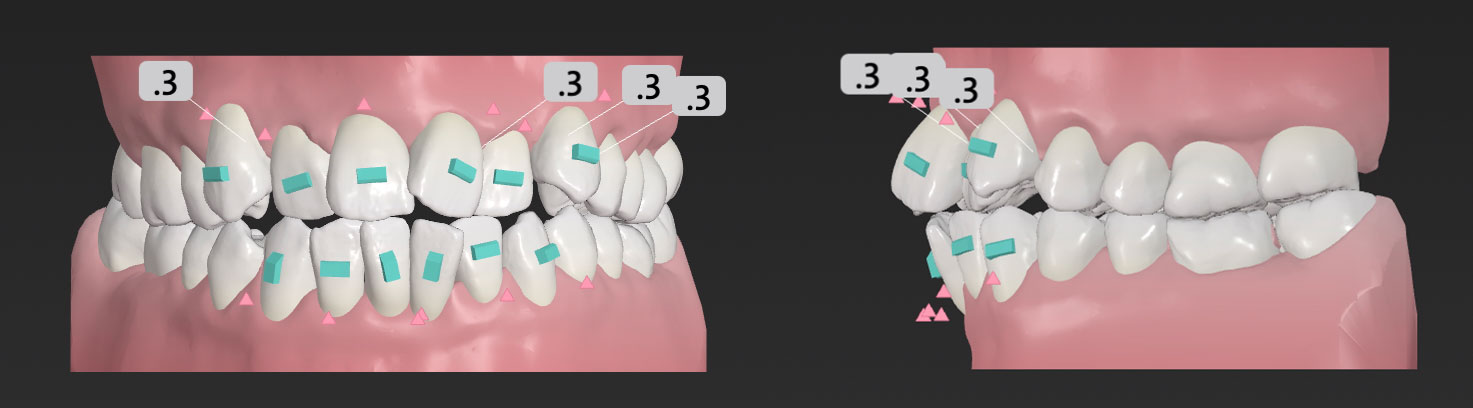

当院では、精密な3Dスキャンによるシミュレーションを行い、治療前に完成形の歯並びを確認します。その計画通りに歯が動いているかどうか、院長が毎回モニタリングしながら進めていきます。

当院では、精密な3Dスキャンによるシミュレーションを行い、治療前に完成形の歯並びを確認します。その計画通りに歯が動いているかどうか、院長が毎回モニタリングしながら進めていきます。

検査結果をもとに、治療のゴールや歯がどのように動いていくのかをシミュレーションします。マウスピース矯正では、3Dで動きを確認できるビジュアルシミュレーションをご覧いただけます。